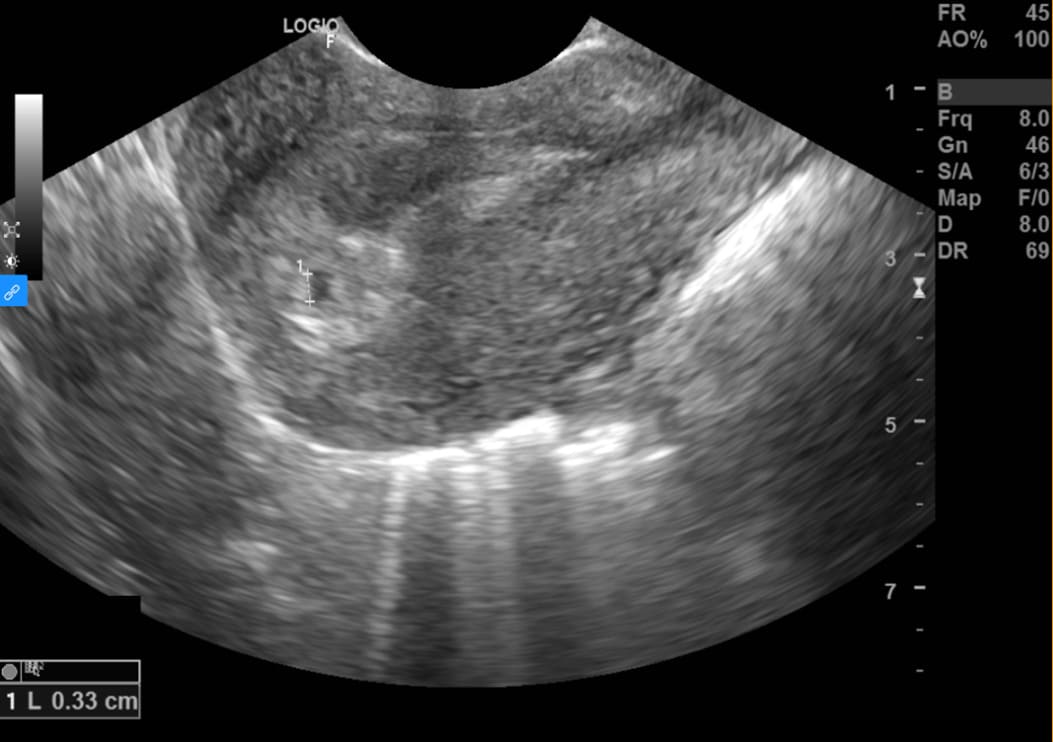

Là loại siêu âm sử dụng loại đầu dò đặc biệt (nhỏ và dài) để đưa vào trong âm đạo, nhằm quan sát rõ nhất các cấu trúc của tử cung – phần phụ, vì đầu dò được đưa vào sát cổ tử cung. Đây là kĩ thuật được ưu tiên trong đánh giá và chẩn đoán thai nhỏ, vì kích thước thai nhỏ, cần một kĩ thuật có độ phân giải cao.

Khác với các kĩ thuật siêu âm đường bụng, kĩ thuật này sản phụ cần đi tiểu hết trước khi siêu âm để bàng quang không chèn vào tử cung phần phụ, giúp quan sát được rõ hơn.

Kĩ thuật có thể được thực hiện từ khi người phụ nữ có dấu hiệu chậm kinh, đến khi thai 12 tuần tuổi, giúp đánh giá xem thai đã vào buồng tử cung hay chưa, số lượng thai là bao nhiêu, có tim thai chưa và tần số tim thai như thế nào, đo kích thước phôi thai để đưa ra dự kiến sinh; ngoài ra siêu âm đầu dò còn đánh giá được tình trạng bánh rau, dây rốn, túi thai, hay các bất thường như tụ dịch – tụ máu dưới màng nuôi, dọa sảy thai, thai ngoài tử cung… Từ đó, các bác sĩ có thể chẩn đoán và xử trí kịp thời cho sản phụ, tránh các biến chứng nguy hiểm.

Siêu âm thai bằng đầu dò âm đạo có thể phát hiện được túi thai khi kích thước còn rất nhỏ